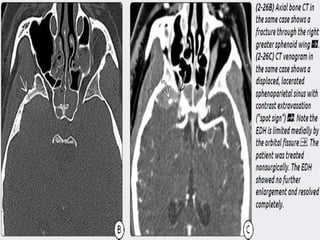

b) Venous EDH- smaller, low pressure, develop

slowly

Most venous EDHs are caused by a skull fracture

that crosses a dural venous sinus and therefore

occur in the posterior fossa near the skull base

(transverse/sigmoid sinus) or the vertex of the

brain (superior sagittal sinus).

In contrast to their arterial counterparts, venous

EDHs can "straddle“ intracranial compartments,

crossing both sutures and lines of dural attachment

and compressing or occluding the adjacent venous

sinuses.

 Several anatomic subtypes of venous EDHs, each

with different treatment implications and

prognosis, are recognized:-

Vertex EDH- Rare , caused by fractures involving

suture and crossing the SSS.

 Anterior Temporal EDH – occur in anterior tip of

middle cranial fossa. Caused by skull base #

involving the greater wing of spenoid or a tripod

fracture(zygomatico-maxillary complex),

disrupting spheno-parietal sinus. Anterior

temporal EDHs remain stable in size and do not

require surgical evacuation

b) Venous EDH-smaller, low pressure, develop slowly Most venous EDHs are caused by a skull fracture that crosses a dural venous sinus and therefore occur in the posterior fossa near the skull base (transverse/sigmoid sinus) or the vertex of the brain (superior sagittal sinus). In contrast to their arterial counterparts, venous EDHs can "straddle“ intracranial compartments, crossing both sutures and lines of dural attachment and compressing or occluding the adjacent venous sinuses.

 Several anatomicsubtypes of venous EDHs, each with different treatment implications and prognosis, are recognized:- Vertex EDH- Rare , caused by fractures involving suture and crossing the SSS.  Anterior Temporal EDH – occur in anterior tip of middle cranial fossa. Caused by skull base # involving the greater wing of spenoid or a tripod fracture(zygomatico-maxillary complex), disrupting spheno-parietal sinus. Anterior temporal EDHs remain stable in size and do not require surgical evacuation